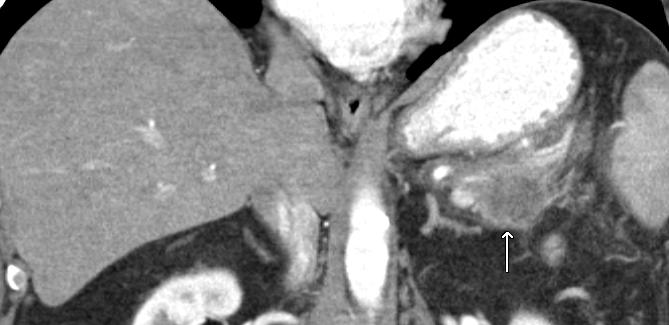

Image: PET/CT scan showing extensive FDG-avid tumor featuring.

PET/CT scan showing extensive FDG-avid tumor featuring